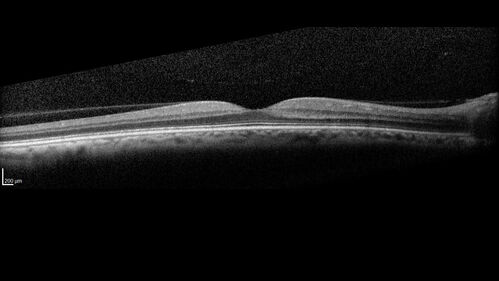

Neuroretinitis left eye - recovered with no therapy - possible B pertussis

57 year old female The patient has had blurred vision in the left eye and there is a haze across the top of the vision.  This started about 2 weeks ago.  The right eye is OK.  She has sleep apnea and uses the machine.  The left eye is becoming more and more painful for the last two weeks.  The pain is like a stabbing in the eye that comes and goes.  She also has some pain on eye movement.  The patient has been going to Moffit for possible reconstructive surgery for the lymphedema.

PMHx – Sleep apnea, Breast Cancer, Adult lymphedema,

Meds: Gabapentin

VA OD: Dcc20/25-1

VA OS: Dcc20/100-2

AC quiet OU.  1 + NS cataract OU

IOP: TP: OD:15 OS:17